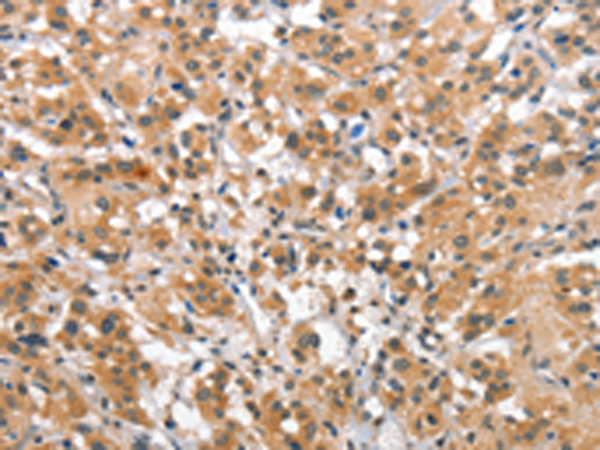

分类: 科研抗体货号: P04693别名: LDS3; LDS1C; MADH3; JV15-2; HSPC193; HsT17436应用: WB,IHC反应种属: Human, Mouse, Rat